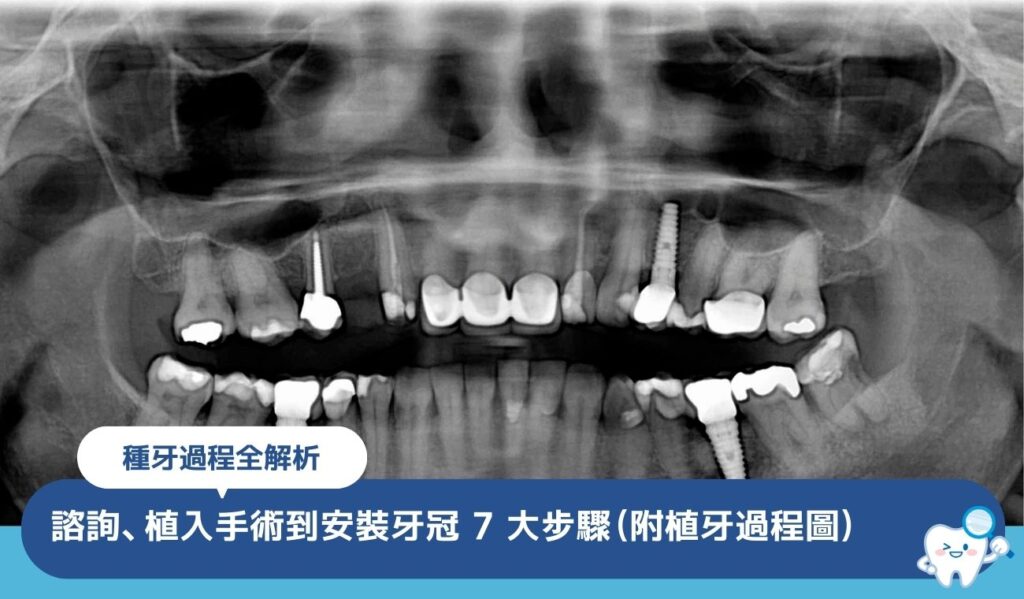

箍牙流程全解析:從諮詢到拆箍 7 大步驟一文看清(附療程時間表)